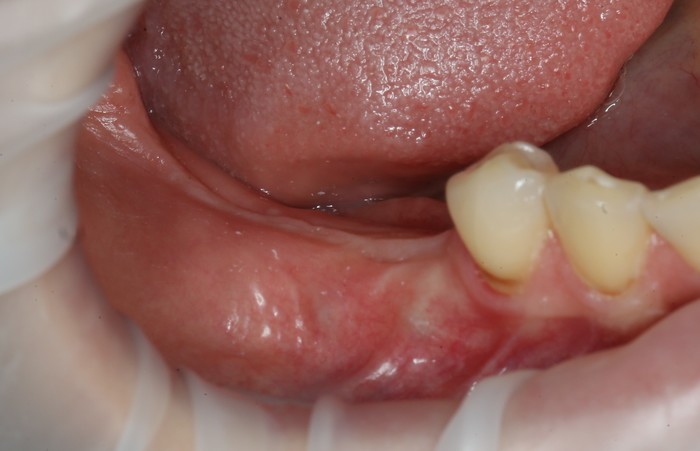

В полости рта ситуация выглядит так:

Отмечается сильная истираемость зубов в связи с длительным отсутсвием полноценного контакта в жевательном отделе.

Отмечается пигментированный зубной налет и отложения солей камней в области зубов на нижней челюсти с язычной стороны.